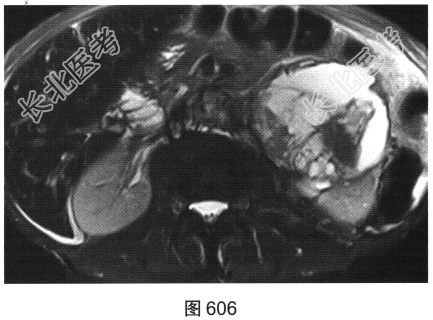

- 多项选择题3.患者进一步行MRI检查,对MRI影像特征描述正确的是( )

A、可见淋巴结转移

B、T2WI以低信号为主

C、增强无强化

D、病灶信号不均匀

E、增强可见分隔状强化

F、T2WI以高信号为主

关注下方微信公众号,搜题查看答案